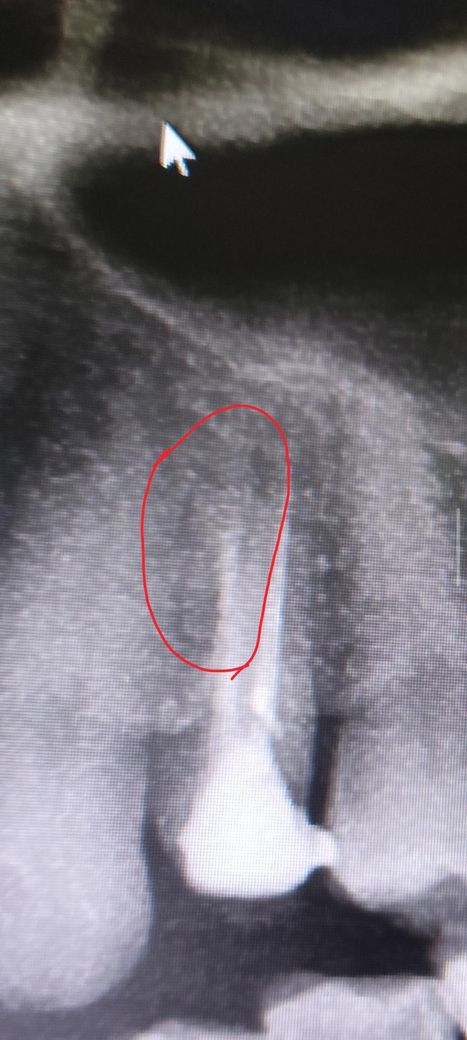

치아파절된거 같은데 발치해야되나요? 사진보시구 답변주심 감사합니다.

뽀족한것을 잇몸으로 동그라미친 부분에 넣어보니 쭉들어가더라구요 아무래도 치아가 사진속 동그라미친 부위모양으로 파절되서 그쪽으로 음식물이 들어가거나 씹을때 파절된

치아조각이 뿌리치조골쪽을 게속 찌르니까 신경과민 예민생겨서

사진속 동그라미친 부위 모양으로 파절된게 거의 확실한거같은데 한번 사진 봐주시면 감사합니다. 혹시 저모양으로 파절됬으면 파절조각만 제거해서 남은치아로

• 1번 째 사진

해당 치아 뿌리가 2개인 형태로 보입니다 maxillary second premolar 2 root 구글에 검색해서 엑스레이 사진이나 실제 사진 참고하시고요

그와는 별개로 신경치료나 재신경치료를 했는데도 증상이 지속되면 어딘가 뿌리쪽에 크랙이 있어서 그럴 수도 있습니다 엑스레이 상으론 명확히 보이진 않으나 증상이 그렇다면 맞을겁니다